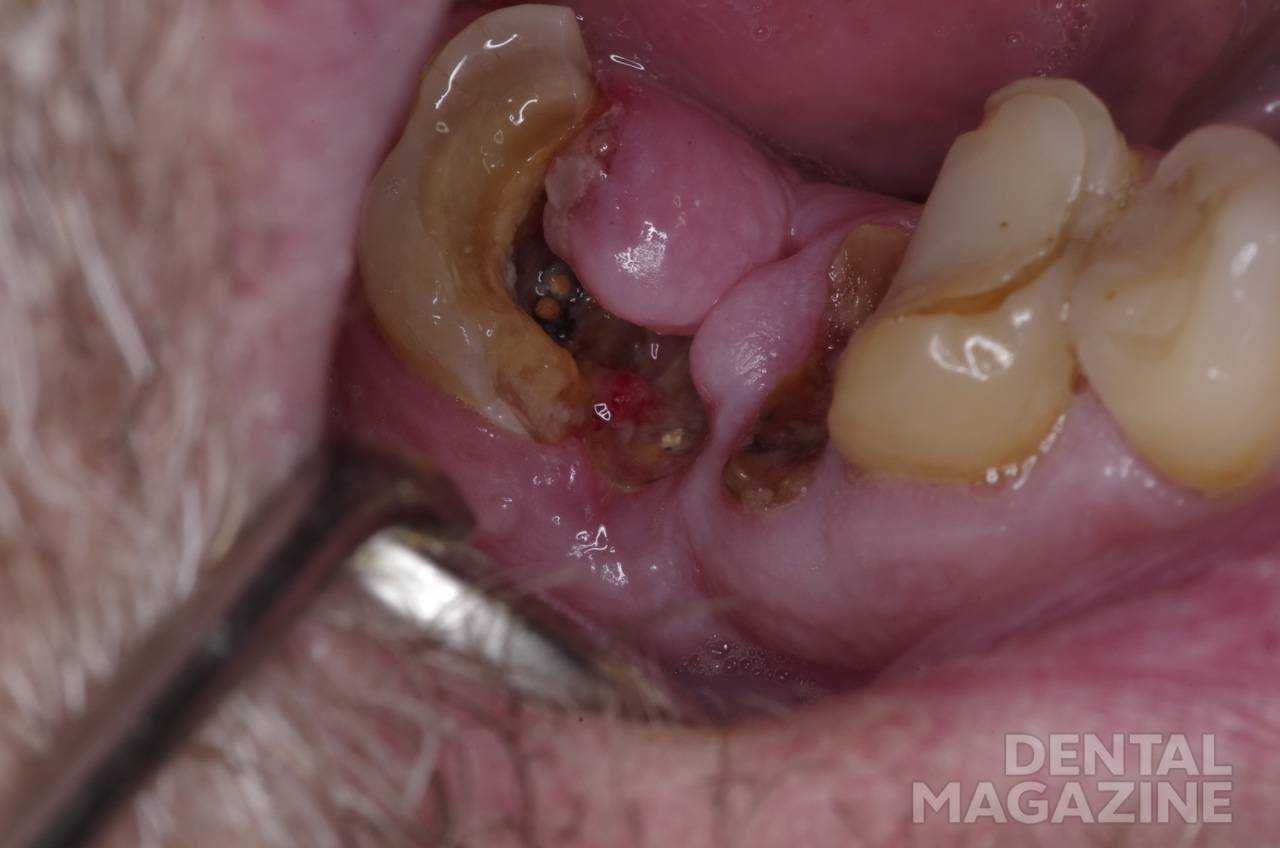

Травмирование корневой пульпы

При лечении пульпита ампутационным методом возможно травмирование корневой части пульпы в случае отсутствии адекватного доступа к устьям каналов (рис. 4).

Рис. 4. Гипертрофированная десна препятствует обзору полости.

Излишнее давление на бор или экскаватор вызовет кровотечение из канала вследствие разрыва сосудисто-нервного пучка. Наложение лечебной прокладки над устьем канала под давлением способствует нарушению кровообращения и функционирования корневой пульпы (рис. 5). В любом случае травма корневой пульпы повышает риск неэффективного лечения пульпита биологическим методом.

Рис. 5. Лечебная прокладка над устьями каналов.

Избежать данного осложнения возможно путем тщательного препарирования кариозной полости с полным иссечением измененного дентина и последующим осторожным удалением крыши пульповой камеры.